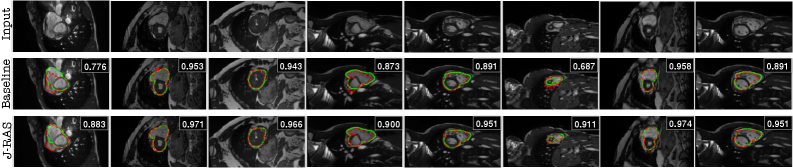

Figure 6: Qualitative segmentation results on the ACDC test set using SegFormer as the baseline and the proposed J-RAS method with SegFormer at Top-k=2k=2. Each column shows an input image, with ground-truth contours overlaid (in green) and predictions (in red). Rows compare the baseline SegFormer (middle) against J-RAS (bottom). The Dice scores above each predicted mask highlight the improved segmentation performance achieved by J-RAS over the baseline.

segmentation outputs against the baseline SegFormer model. Representative examples from the ACDC test set are presented in Figures (6, 7, 8, 9), with results shown at Top-k=2k=2.

Mask-Level Improvements. Figure 8 highlights improvements at the mask level, where each row shows the input image, the ground-truth mask, the baseline SegFormer prediction, and the J-RAS prediction. The Dice scores above each predicted mask demonstrate that J-RAS consistently yields more accurate segmentations. In challenging cases with small or low-contrast cardiac structures, the baseline often produces incomplete or fragmented predictions. At the same time, J-RAS generates more complete and coherent masks (e.g., improving

Dice from 0.687 to 0.911). Even in cases where the baseline already performs well, J-RAS further refines the predictions, leading to consistent accuracy gains.

Refer to caption

Figure 8: Comparison of segmentation results using SegFormer as the baseline and the proposed J-RAS method with SegFormer at Top-k=2k=2 on the ACDC test set. Each row shows the input image, ground truth mask, baseline SegFormer, and J-RAS prediction. The Dice score for each predicted mask is reported above the corresponding output, illustrating the performance improvement of J-RAS over the baseline.